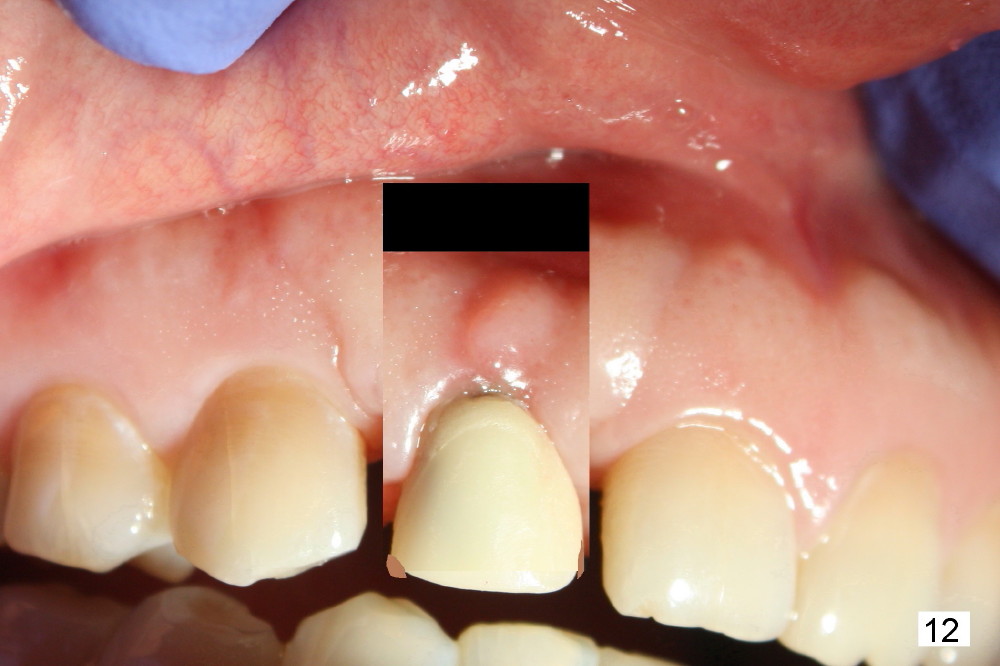

Fig.7,8 show the provisional 10 days and 1.5 months postop, respectively. When the provisional is removed, the implant/abutment is buccally malpostioned (Fig.9). It appears that segmental osteotomy is necessary. Fig.10 shows incision design. The implant and bone complex is to be moved to an ideal position (Fig.11,12). A block graft is inserted apically for internal fixation. An ortho wire is used for external fixation.